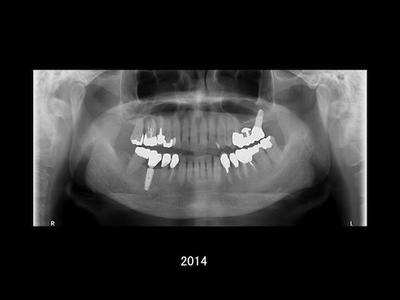

19年間の経過観察より

治療開始から現在まで、およそ19年が経過しました。 これまでの観察では、インプラント周囲の骨の状態も安定しており、セラミックの破折もなく、良好な状態を保っています。

もちろん良好な状態が続いている背景には、患者さんご自身による丁寧な日々のケアがあります。 加えて、3ヶ月に一度のチェックを通じて継続的に口腔内の変化を把握し、必要なタイミングで処置を行えたことも良かったのではないかと感じています。